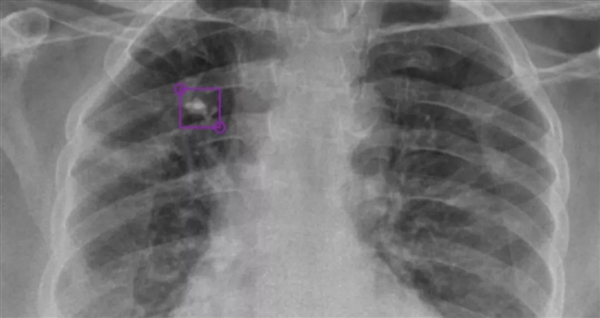

DeepTek AI模型檢測到的右上葉肺部鈣化結(jié)節(jié)

DeepTek希望通過AI驅(qū)動的放射平臺,大大提升全球在醫(yī)學(xué)影像診斷領(lǐng)域的能力,為此開發(fā)了全新的DxTB工具,用來篩查肺結(jié)核的X射線圖像,并標(biāo)記病例,以供醫(yī)學(xué)專家進(jìn)行優(yōu)先檢查。